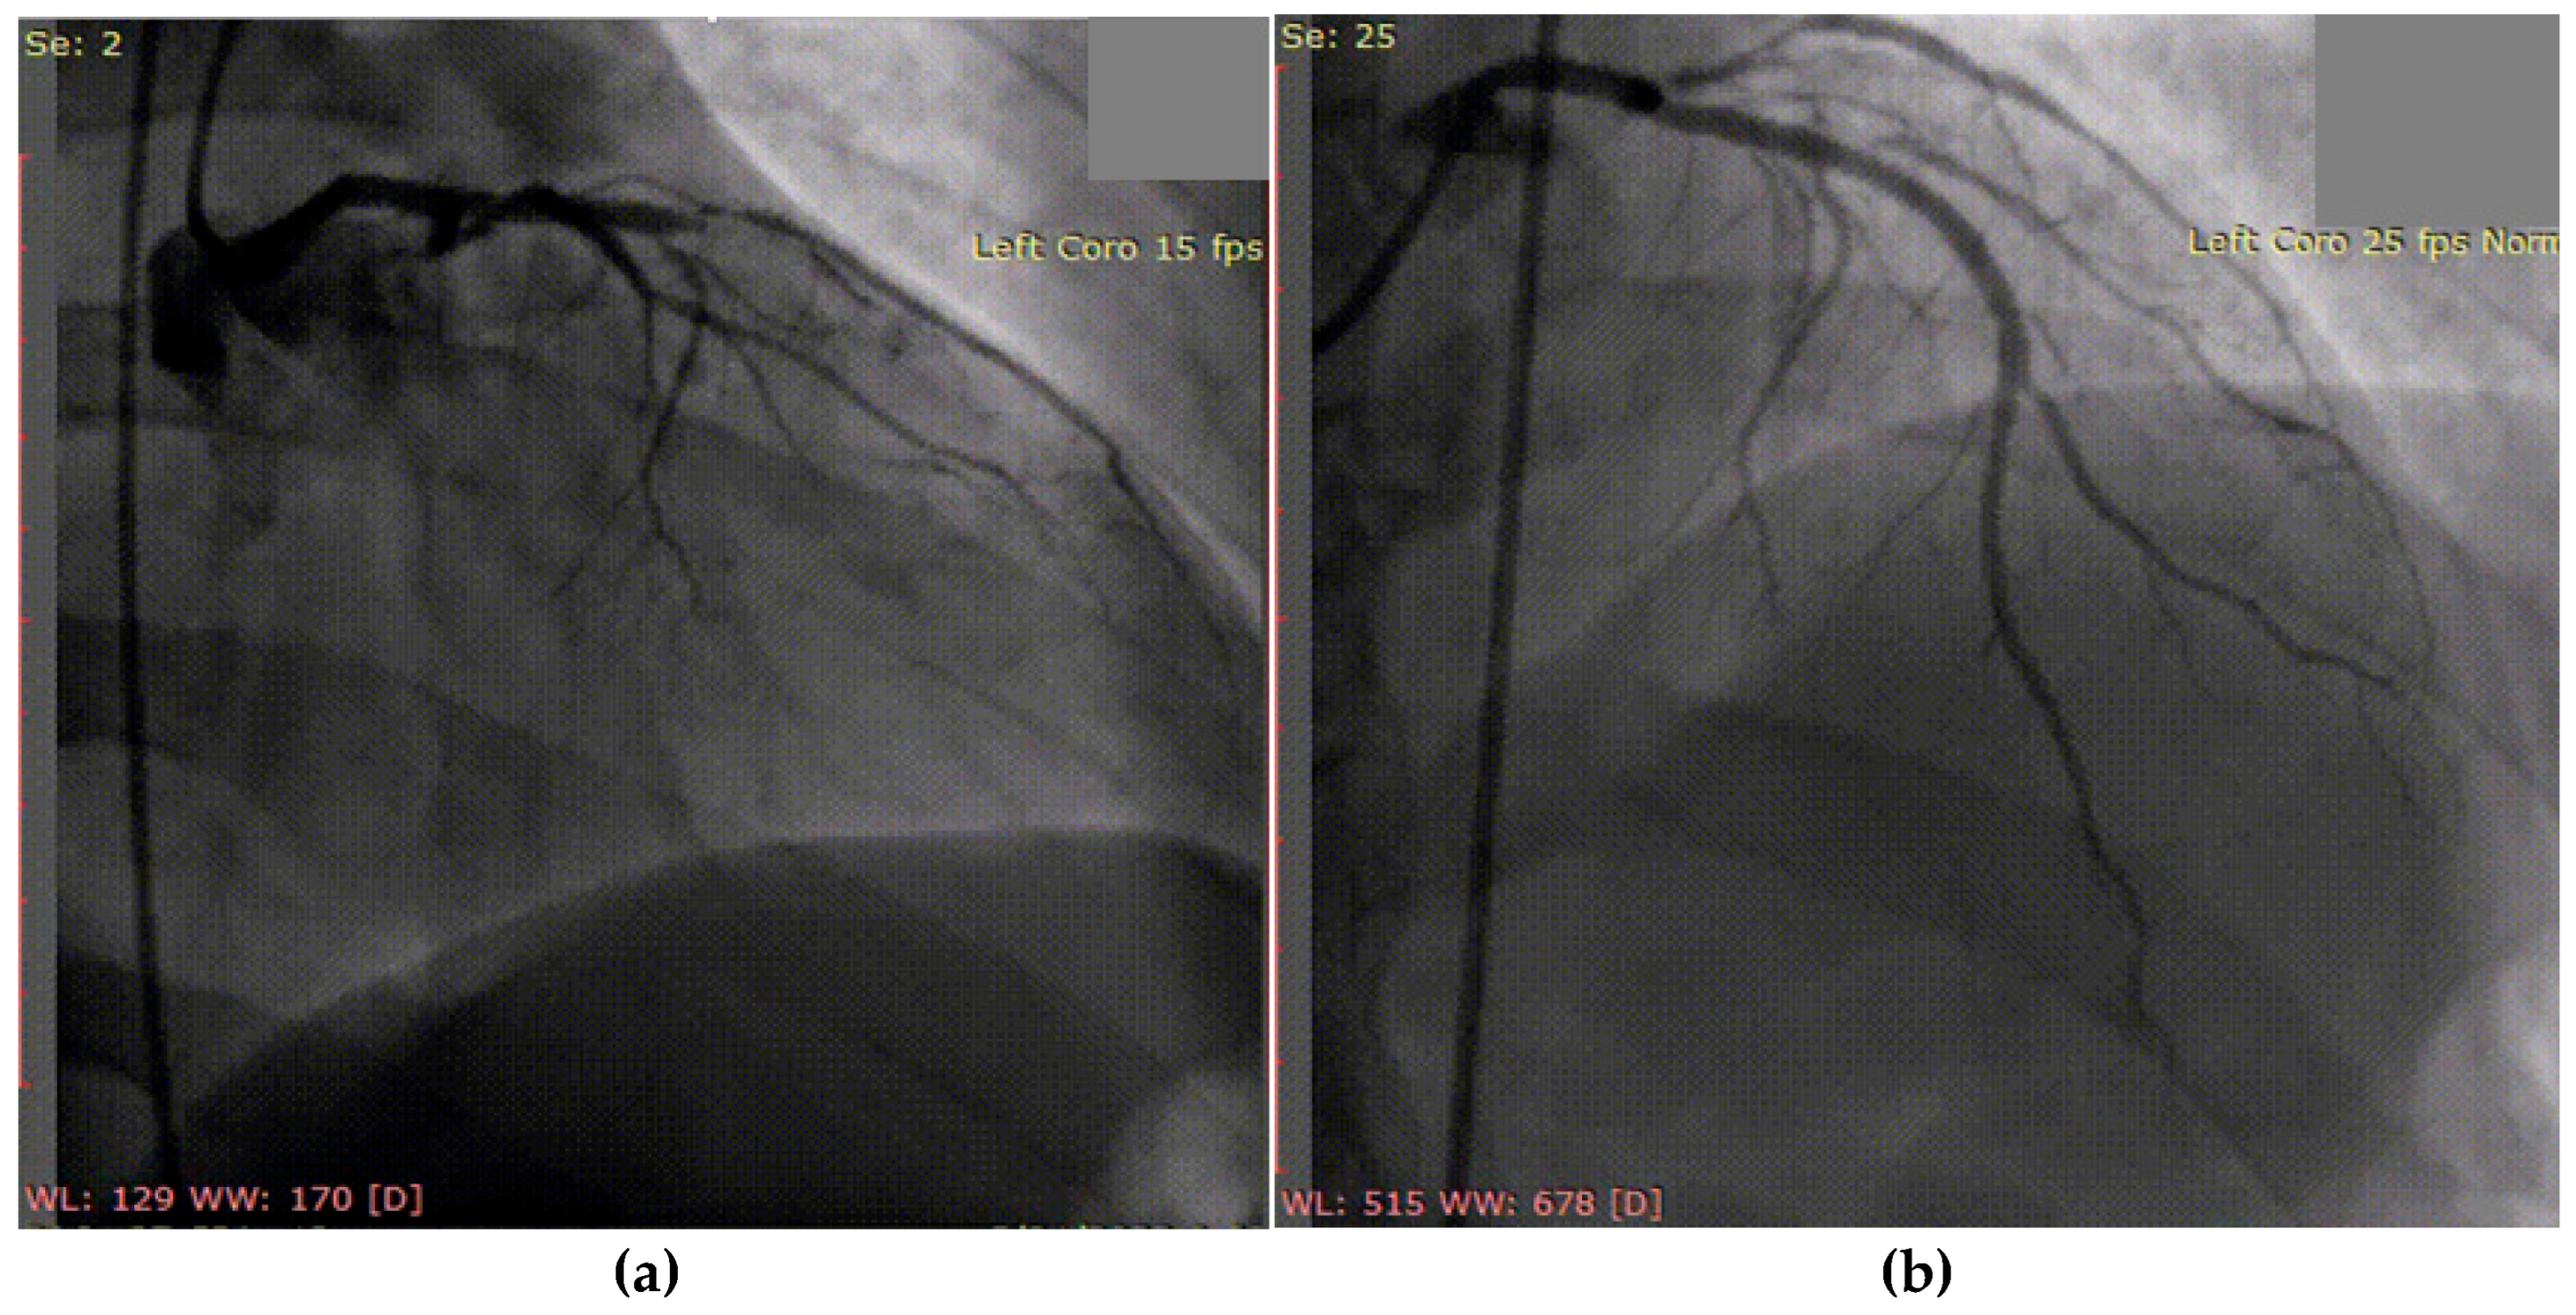

3.1. Case 1

3.2. Case 2